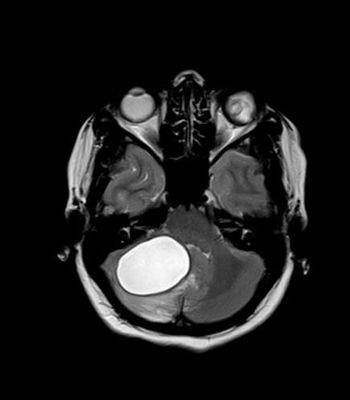

Case history: A 29-year-old female presented in emergency department with recently aggravated headache and vomiting associated with difficulty in walking for seven days.